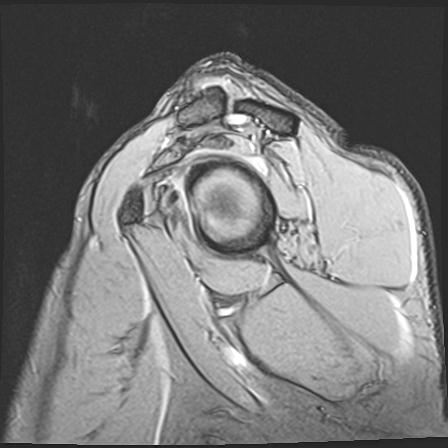

60058 3/9 11/4 右肩 2R+MRI 73歳男性 肩腱板損傷